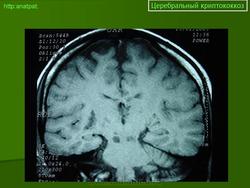

Церебральный криптококкоз.

Приложения:

55.kriptokokkovyy_meningit..jpg